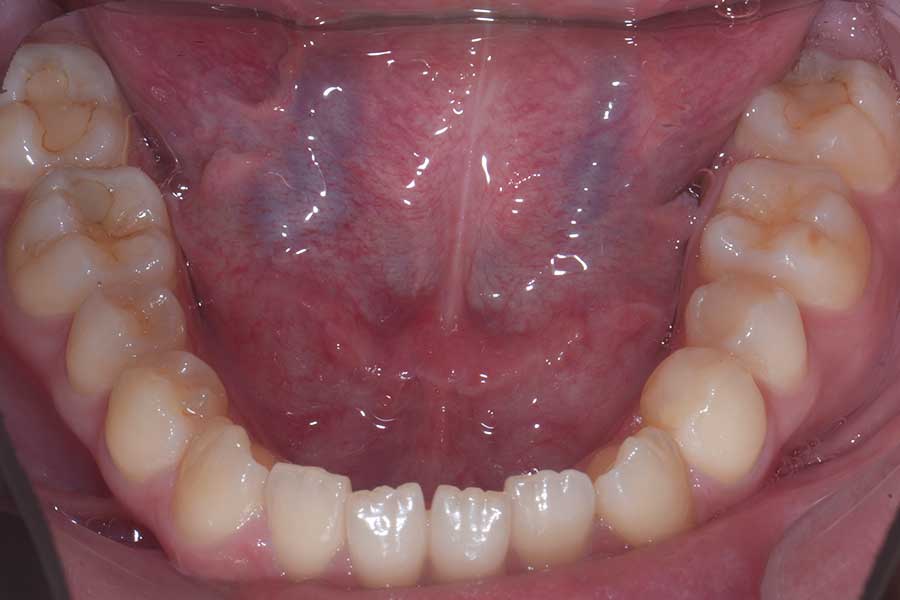

治療前

主訴 前歯で咬み切れるようになりたい

治療内容 ハーフリンガル矯正(上顎裏側・下顎表側矯正)